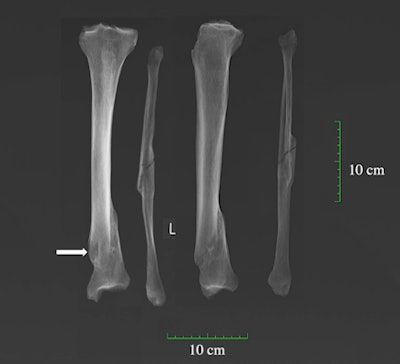

Another friar had lived with defensive fractures on his arm and signs of blunt force trauma to his skull. Such violence-related skeletal injuries were found in about 4% of the population, including women and people from all social groups. One older woman buried in the parish grounds appeared to bear the marks of lifelong domestic abuse.

"She had a lot of fractures, all of them healed well before her death. Several of her ribs had been broken as well as multiple vertebrae, her jaw, and her foot," said Dittmar. "It would be very uncommon for all these injuries to occur as the result of a fall, for example. Today, the vast majority of broken jaws seen in women are caused by intimate partner violence."